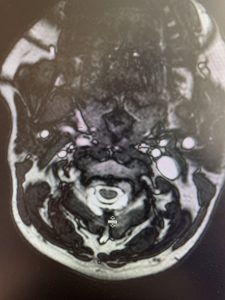

This 57 year-old male presents with severe neck, left shoulder and arm pain and weakness in his hand since being involved in a motor vehicle accident nine months prior. The patient had subsequent left shoulder surgery although he still complained of pain postoperatively and his weakness persisted. He was on no blood thinners. He underwent imaging. The cervical spine MRI revealed an extensive dorsal epidural collection from C1-2 through C5 with associated spinal cord compression. In addition there were multisegmental degenerative changes with foraminal stenosis worse at C4-5 (Fig. 1a and 1b).

(1a) Sagittal and axial T2-weighted cervical MRI demonstrating extensive dorsal epidural collection with hyperintense signal consistent with fluid causing spinal cord compression.

(1b) Hyperintense signal (arrow) at the C3-4 interspinous space consistent with ruptured interspinous ligament,C4-5 (Fig. 1a and 1b).

The fluid was possibly consistent with CSF versus chronic hematoma. The patient was also noted to have a high signal within the interspinous space of C3-C4. This high signal was consistent with a ruptured C3-4 interspinous ligament. Cervical flexion-extension x-rays demonstrated 6 mm of widening of the C3-4 interspinous space on flexion x-ray consistent with cervical instability (Fig. 2a and 2b).